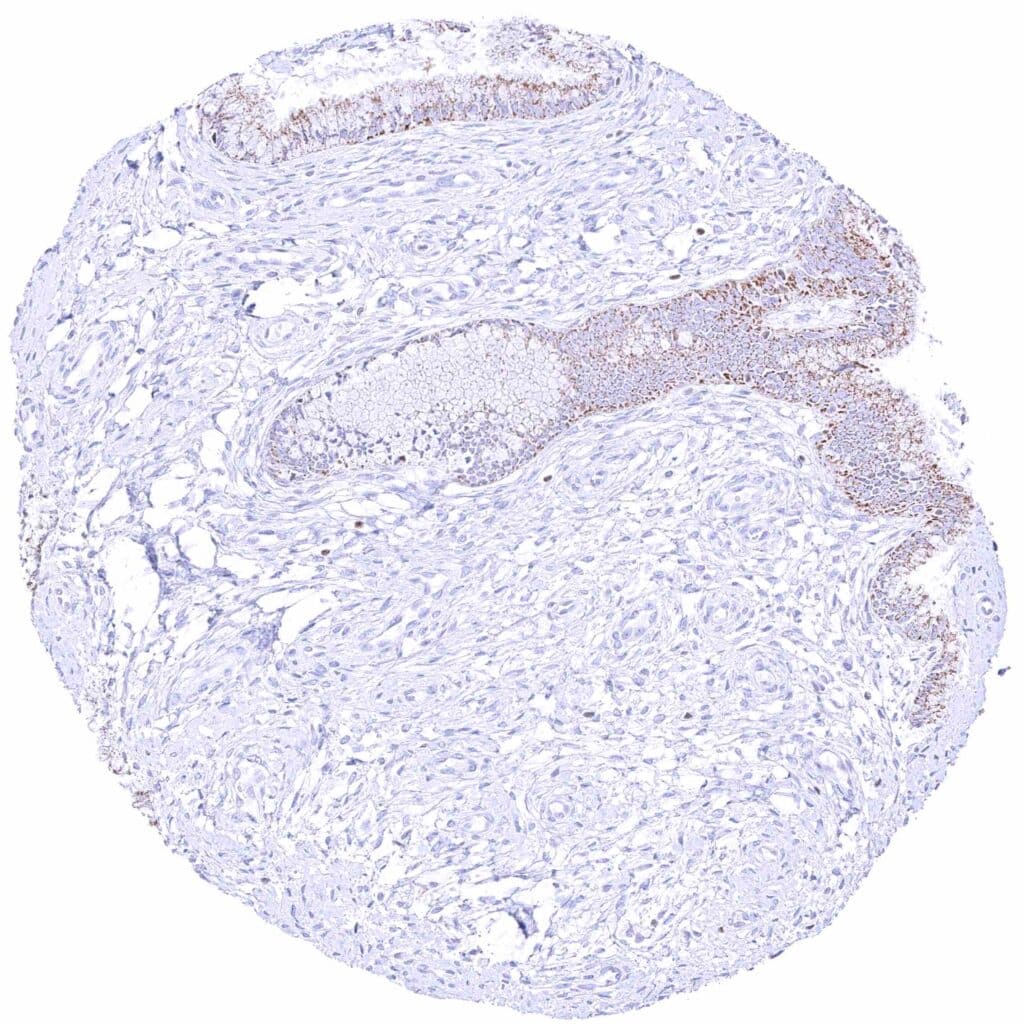

Prostate – Weak to moderate, nuclear GATA3 staining of basal cells. .jpeg